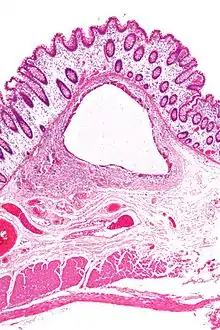

- Pneumatosis intestinalis, air or gas cysts in the bowel wall